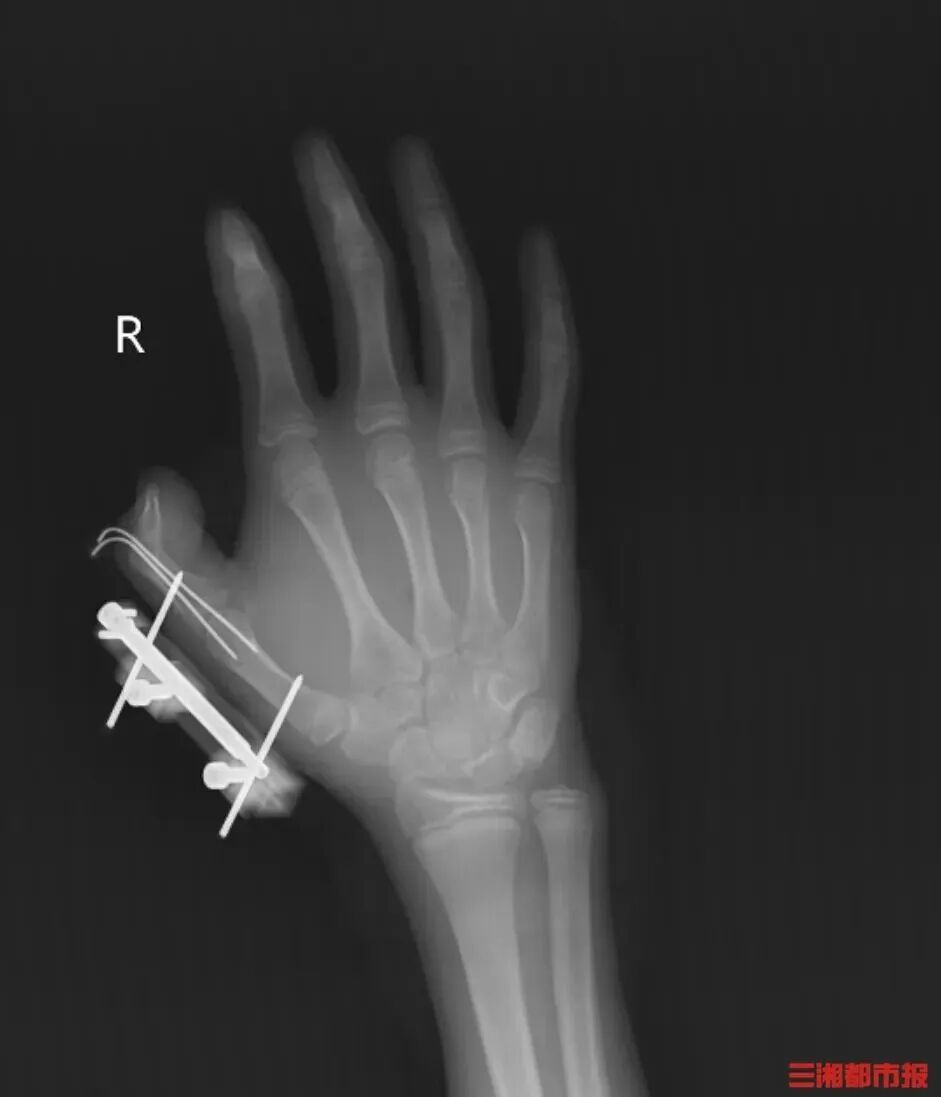

把干冰当玩具摇

14岁少年手指被炸得深可见骨